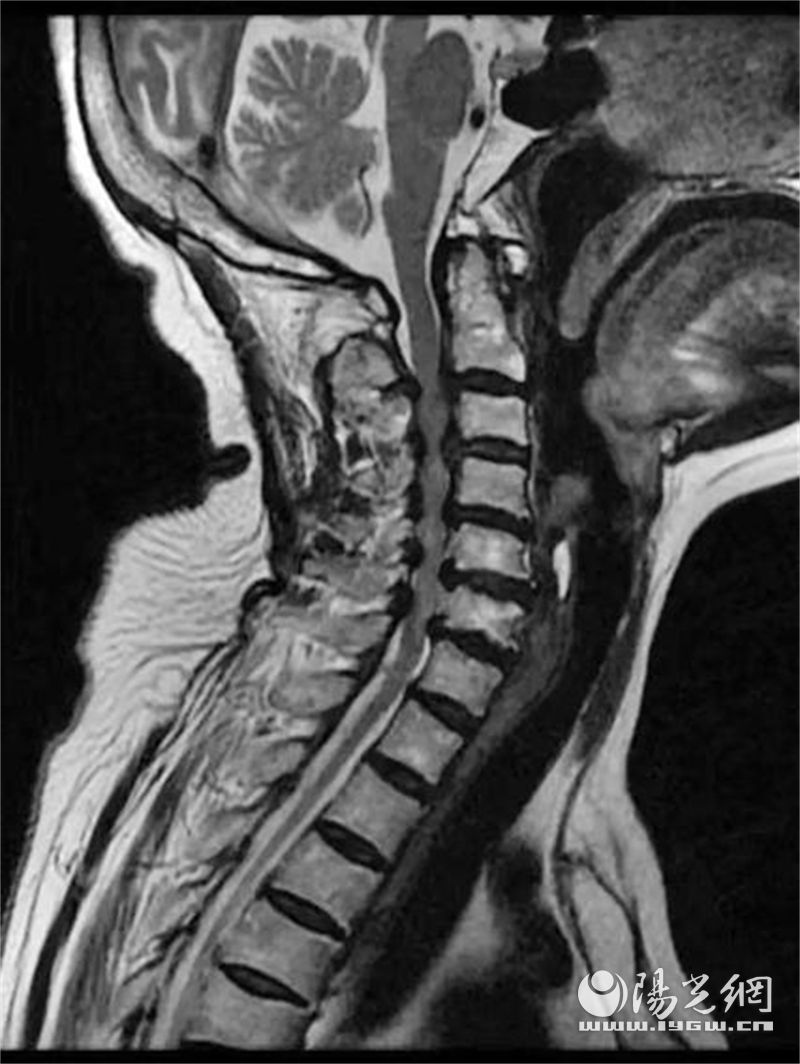

提起颈椎病,大多数人会理解为“脖子酸痛”,贴膏药、理疗按摩是人们的常见选择,很难将颈椎病和瘫痪这样严重的字眼联系在一起。但在一月余前,67岁的博阿姨不慎摔了一跤,当时就瘫坐在地没有办法站立,双腿失去控制,同时伴有头痛、头昏,几乎到了瘫痪状态。送西安市长安区医院急诊后,经骨科三病区赵爱国医生会诊仔细检查,根据患者的查体及影像学检查判断为严重的脊髓损伤伴随不完全瘫痪。

博阿姨有糖尿病病史,身体状况并不理想。经医师、麻醉、护理等团队讨论,深度分析病情,制定了详细的手术方案。手术使用了控制性降压技术,采取后正中切口,通过后正中入路劈开棘上韧带,显露颈3到颈7节段椎板,用磨钻在关节突内侧切开颈3到颈7节段两侧椎板,通过棘突提拉揭开4个节段椎板,完成多节段椎管减压,在颈3到颈7椎体侧块打入螺钉固定,完成后路钉棒固定,随后手术顺利完成。

术前术后对比